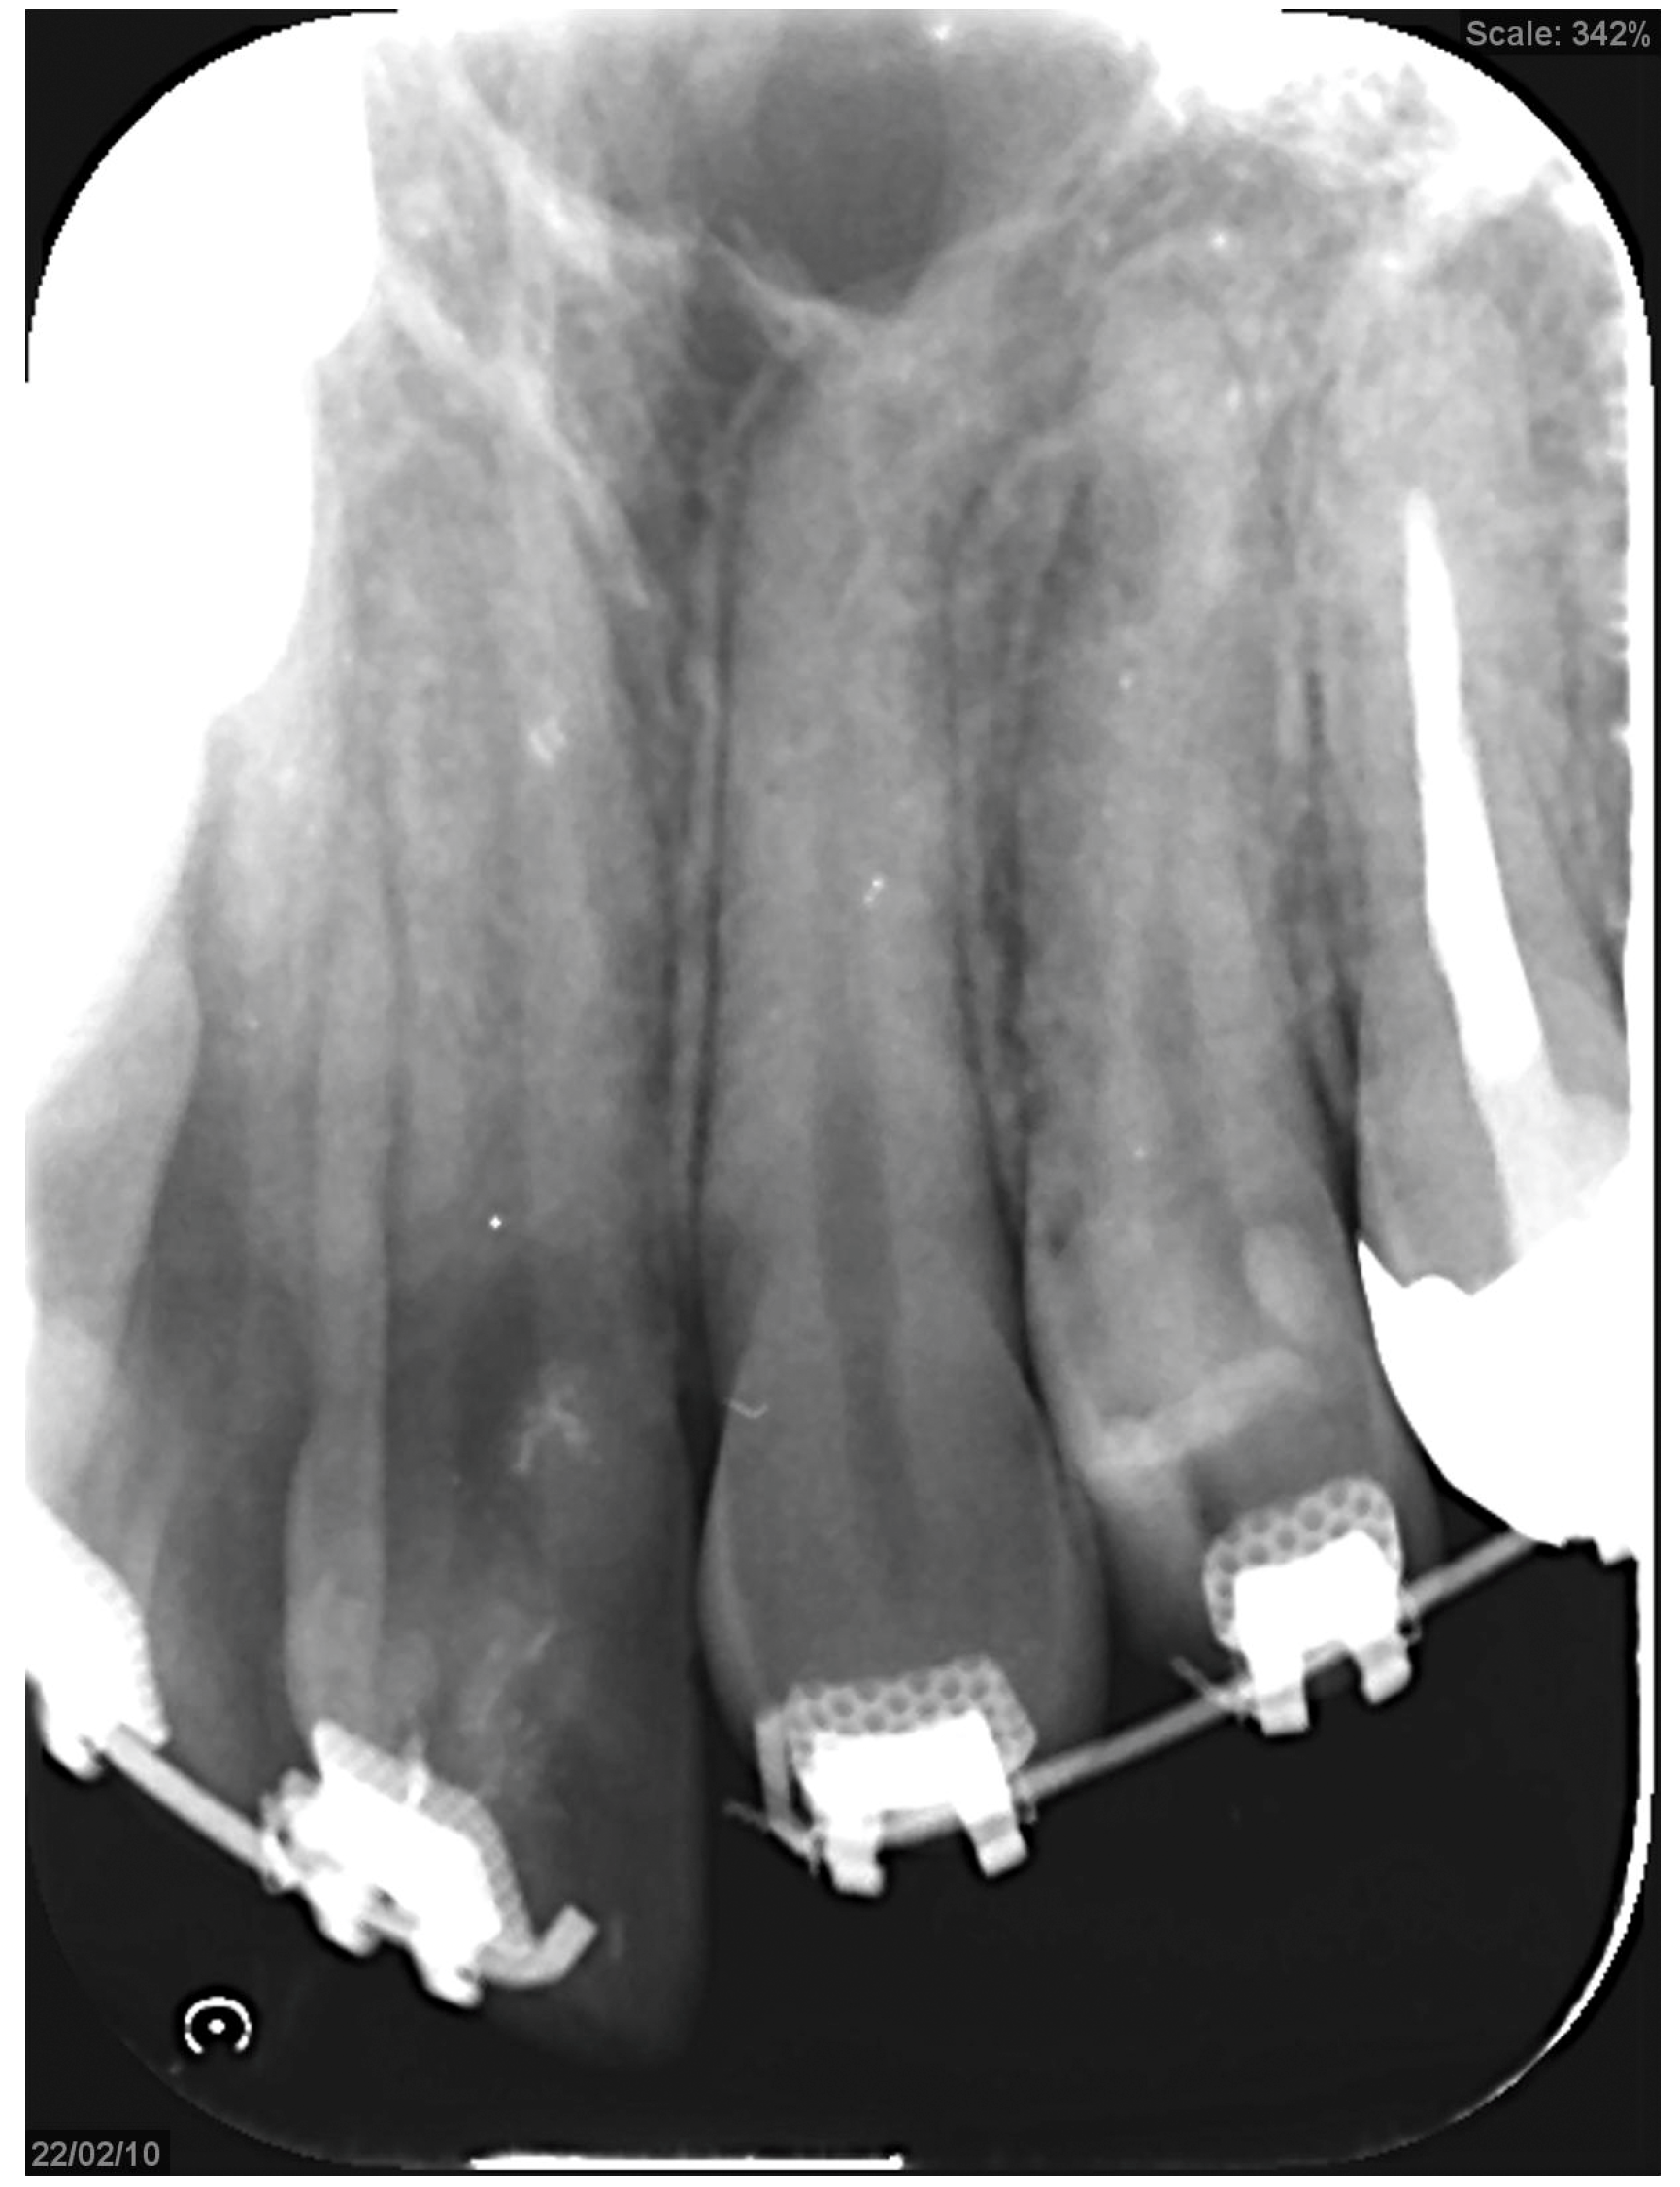

Figure 7.

Preoperative intraoral photograph and radiographs and CT. (A) Intraoral photographs. (B) Panoramic radiograph. (C) Cephalograms and CT.

Treatment progress: During preoperative orthodontic treatment, owing to the significant asymmetry in the left and right maxillary dental arches, leveling was initiated using a sectional arch, dividing the maxilla into two segments: from the right second molar to the left central incisor and from the left canine to the left second molar. The mandibular right lateral incisor, which exhibited lingual displacement, was extracted, and a multi-bracket device (0.022 slot pre-adjusted appliance) was placed. After leveling was completed in the maxilla, the treatment transitioned to a continuous arch to minimize intraoperative movement while improving the arch width. Subsequently, to facilitate the multi-segment Le Fort I osteotomy, an open coil spring was placed between the left central incisor and the canine to gain the necessary osteotomy width. In the mandible, the extraction space from the right lateral incisor was used to improve crowding and space closure was performed (Figure 5). Dental photographs taken just before surgery confirmed that a 3.0 mm space was achieved for the surgical procedures necessary for the multi-segment approach, at which point the arch was switched to a sectional arch (Figure 6). After 15 months of treatment, preoperative orthodontics were nearly completed, and preoperative records were obtained. Crowding in the mandible was resolved, and the arch of the maxilla approached an ovoid shape with approximately 4.0 mm of expansion in width; however, the occlusion on the right side remained a crossbite (Figure 7). During orthognathic surgery, a rolling movement of 6.0° to the right was performed around the left first molar to correct the left-sided cant of the occlusal plane. A 5.0° posterior impaction centered on the anterior nasal spine and a 2.0 mm parallel shift to the left were also performed to improve the deformity and align the midline. Furthermore, a multi-segment Le Fort I osteotomy was performed to expand the maxilla by 5.0 mm from the left canine to the second molar, correcting the maxillary and mandibular arch asymmetry. During this process, a releasing incision was made at the palatal scar site, using a chisel and mallet for osteotomy.